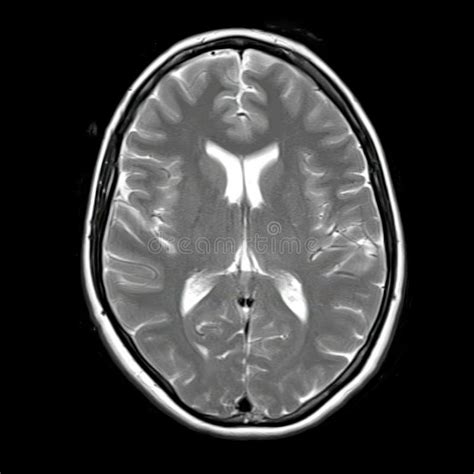

Neuroimagen y Factores Predictivos de Secuelas

Las alteraciones en los estudios de neuroimagen son comunes en pacientes con infección congénita por CMV sintomática, estando presentes en más del 60% de los casos. Estos hallazgos pueden incluir:

- Calcificaciones cerebrales (especialmente periventriculares).

- Ventriculomegalia (dilatación de los ventrículos cerebrales).

- Vasculopatía lenticuloestriada.

- Alteraciones de la sustancia blanca.

- Trastornos de la migración neuronal.

- Atrofia cortical.

- Quistes periventriculares.

- Hipoplasia cerebelar.

Un estudio comparó pacientes con y sin secuelas neurológicas. Se encontró que la presencia de clínica neonatal y alteraciones en los estudios de neuroimagen fueron significativamente más frecuentes en el grupo con secuelas. Ciertos hallazgos en la neuroimagen, como la presencia de alteraciones de la sustancia blanca o trastornos de la migración neuronal, podrían predecir las secuelas neurocognitivas en pacientes con infección congénita por CMV.